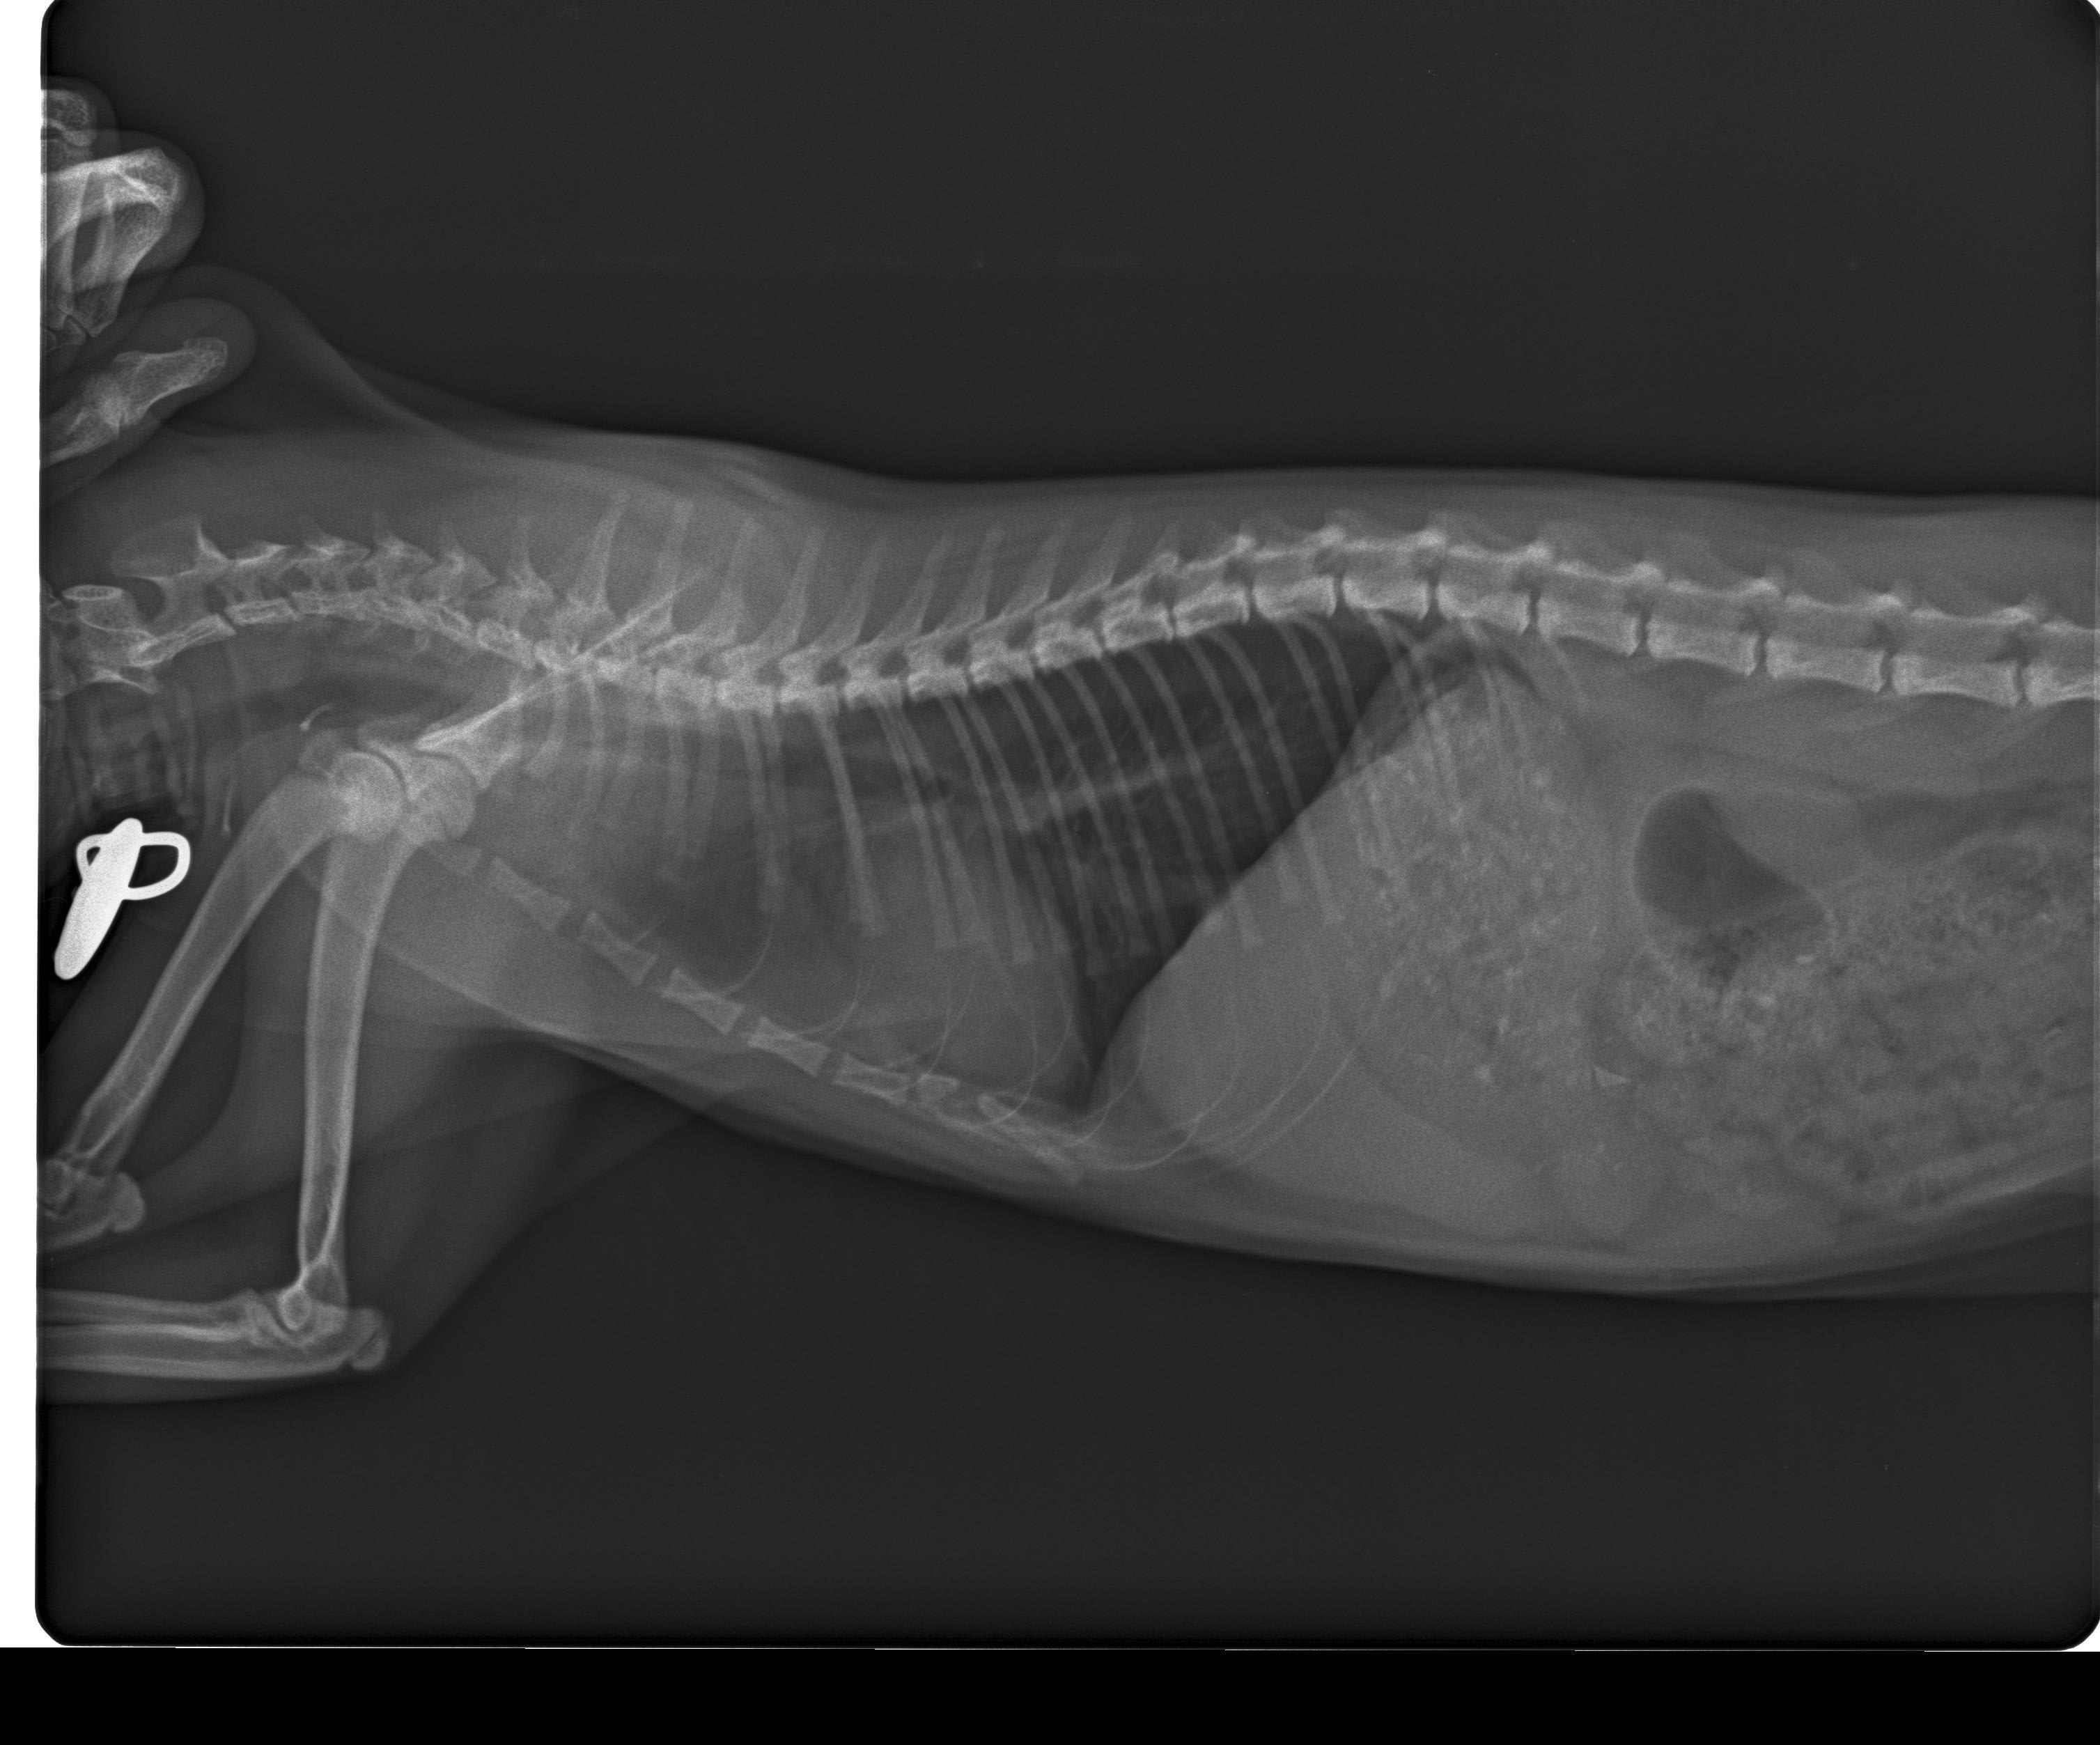

hello, i noticed that my cat (6 months) breathe rate is high even in rest time 60 to 70 per minute. i took it to vet, he said normal, the whether is hot. i took the cat yesterday to another vet, he made an x-ray for lungs and he said there is some fluid in lungs. he gave me an antibiotic for the cat "Marbocyl P5mg" with some instructions, and he said he will be better in 3 days. pls tell me if this is right. i will attach the xray pic thank you in advance

It is always hard to look at x-rays on a computer screen like this. I am not seeing clear fluid, but I can't be certain. Marbocyl is a type of antibiotic that can be used with bacterial pneumonia. Other causes of increased respiratory rate are being hot (though this isn't the most common cause), infection (bacterial and viral), heart disease (needs a heart ultrasound), asthma, pain, anemia, kidney disease, among others. If the antibiotics do not show improvement in another day or two, I would take Leo back to the vet for additional testing (including other views of the chest x-rays).